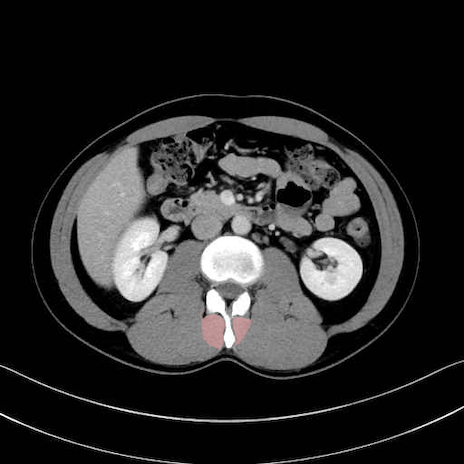

多裂筋 (Multifidus)